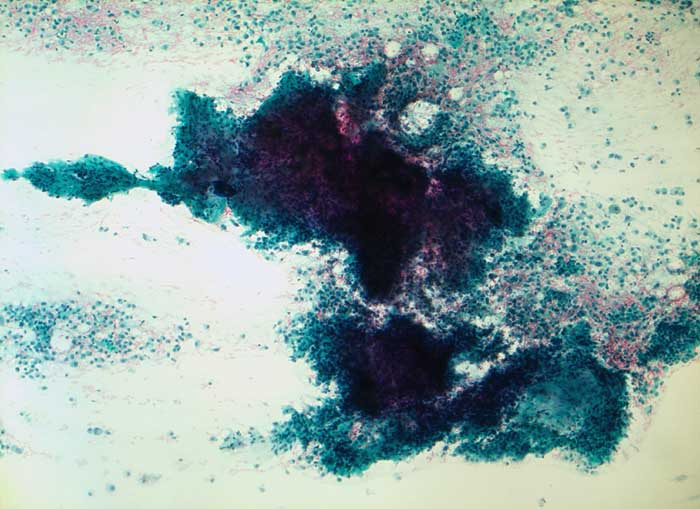

Pleomorphes Adenom

benigner Tumor

Speicheldrüse

Feinnadelpunktat der Speicheldrüse: Wolkige zyanophile Matrixanteile. Matrix und Epithelien bilden zusammen palmwedelartige Formationen.

Parotistumor unklarer Dignität

96% der pleomorphen Adenome werden zytologisch korrekt diagnostiziert.

Zytologie

50